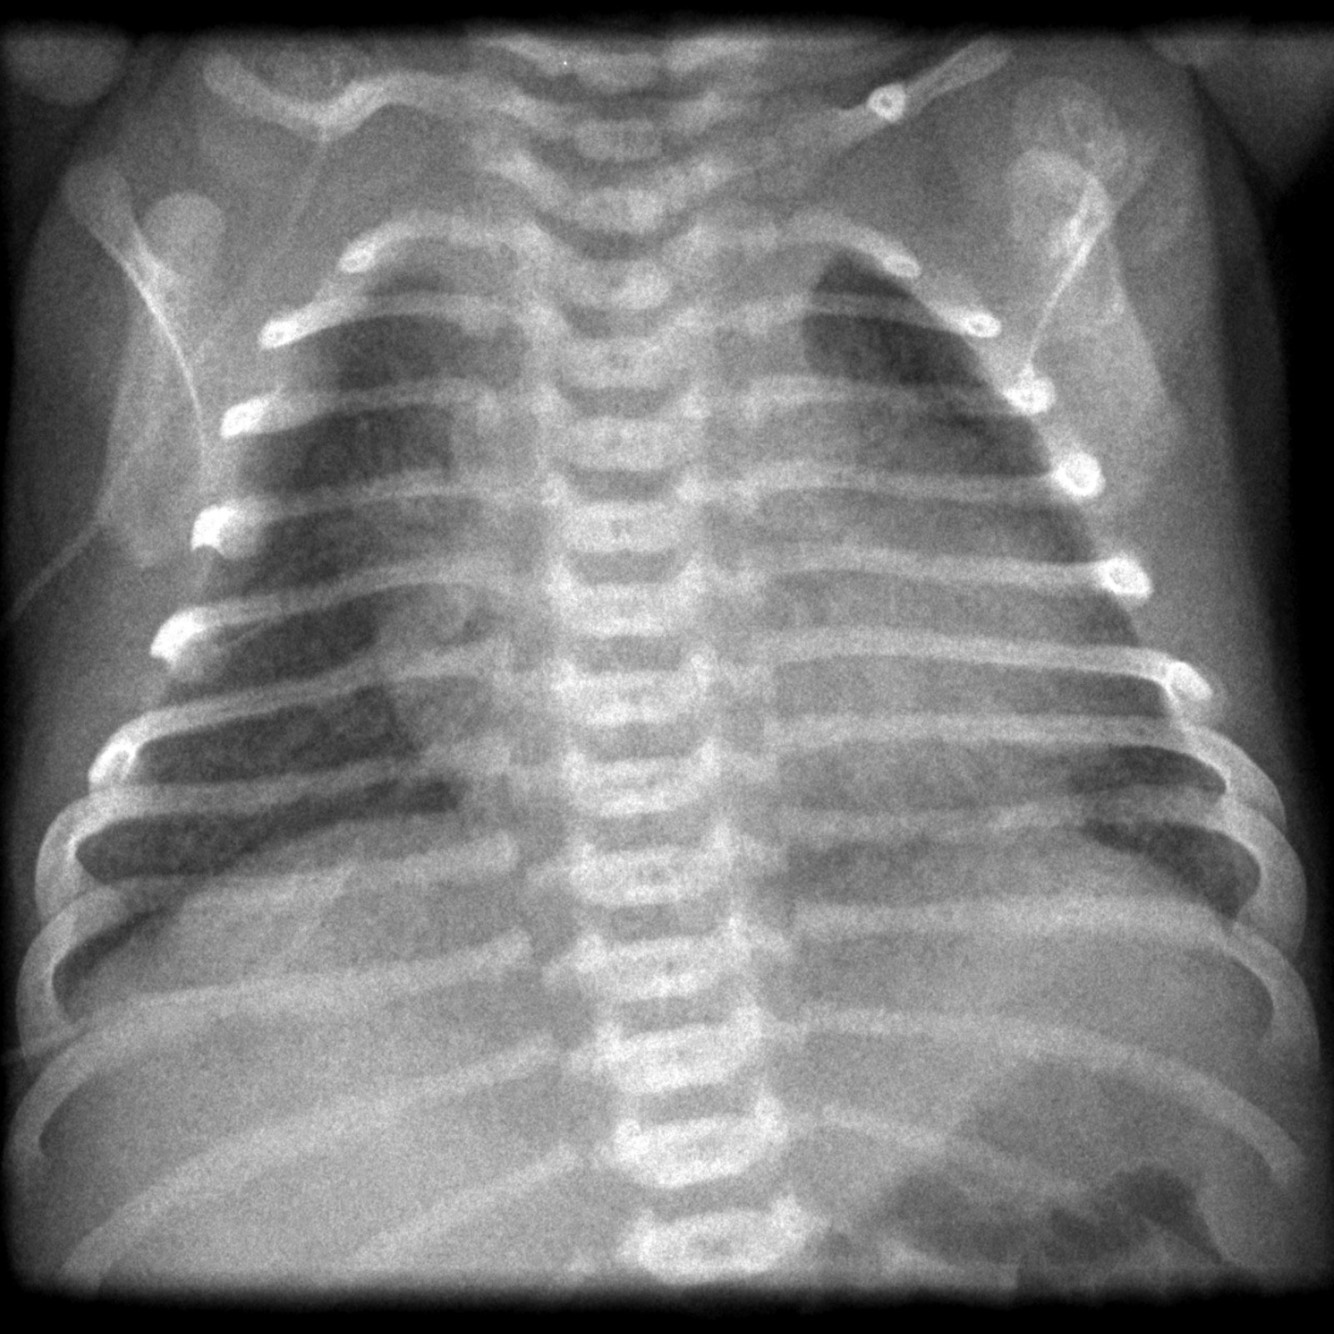

Newborn infant with respiratory distress.

DIagnosis and key xray findings.

Meconium aspiration.

Linear densities emanating from the hila and increased lung volumes.

Most common in term infants with in utero or intrapartum stress.